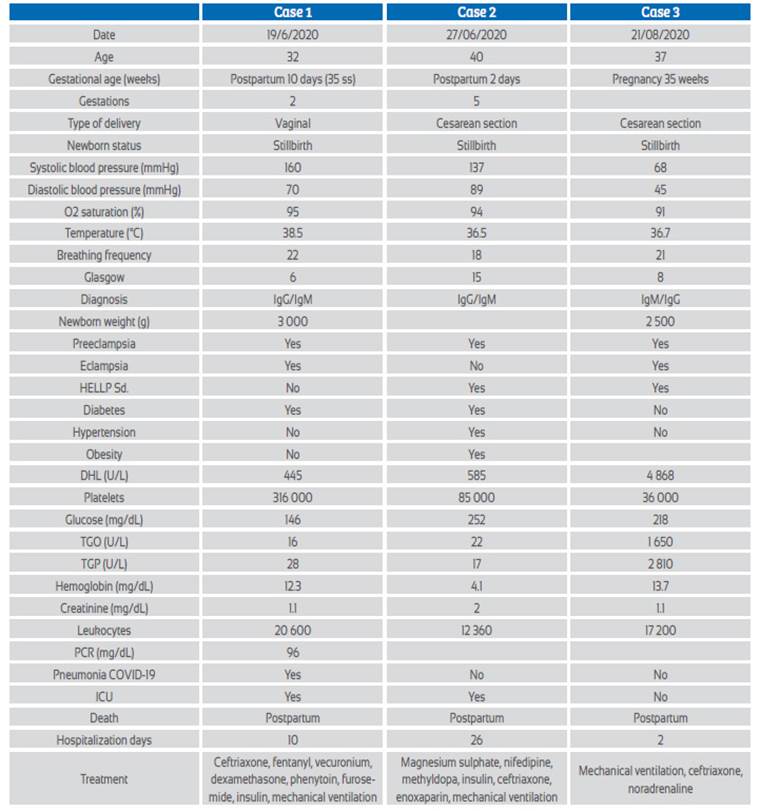

Brain multislice spiral tomography (MST) with coronal and sagittal reconstructions (Figure 1) showed extensive right cerebral infarction (in the middle cerebral artery (MCA) and the anterior cerebral artery (ACA) territory, with a large mass effect, conditioning deviation of the midline by 14 mm to the left and partial collapse of the supratentorial ventricles. Increase density of the MCA was evidenced, probably related to thrombus (Alberta Stroke Program Early CT Score (ASPECTS):0). Chest MST with coronal and sagittal reconstructions showed typical signs of Covid-19 ("ground glass", vascular thickening, cobblestone pattern, parenchymal bands and bilateral consolidations predominantly left). CORADS: 513.

Figure 1 Case 1. Brain tomography without contrast (with coronal and sagittal reconstruction): extensive rigth cerebral infarction (in the territory of the middle cerebral artery (MCA) and anterior cerebral artery (ACA)), with a large mass effect, conditioning a deviation of the midline by 14 mm to the left and partial collapse of the supratentorial ventricles. Increased MCA density is evidenced, probably related to thrombus (Alberta Stroke Program Early CT Score (ASPECTS ):0).

Neurological symptoms due to COVID-19 range from anosmia to ischemic stroke or intracerebral hemorrhage. It is reported that due to hypercoagulability up to 5.7% of patients have cerebrovascular accident and 2.8% ischemic stroke15. Of hospitalized patients with COVID-19 and neurological compromise, 77% have an ischemic component. Because the complication occurs in the great vessels, 84.2% improve with Solumbra technique mechanical thrombectomy, obtaining substantial improvement in permeabilization, with score TICI> 2B/3 (16) . In our cases, coagulopathy with ischemic stroke was found in the territory of the right anterior and middle cerebral arteries in 33.3% of cases, associated with eclampsia and pneumonia due to COVID-19 (CORADS-5). In these cases, teamwork with neurology, neurosurgery, cardiology and radiology specialists is necessary, as well as the use of NIHSS clinical and ASPECT carotid arteries Doppler, cardiac Doppler radiological scales, and adequate thrombolysis, measurable with mTICI (modified treatment in cerebral infarction score), and early decompressive craniotomy.

Second, the possibility that preeclampsia be considered a comorbidity associated with mortality from COVID-19. Third, stillbirth may be common and should be considered and prevented. Fourth, severe preeclampsia in the presence of symptomatic COVID-19 has high mortality, due to the severity of both. Fifth, brain tomography is essential in early diagnosis and would help to quickly initiate the management of postpartum women with ischemic or hemorrhagic brain involvement.